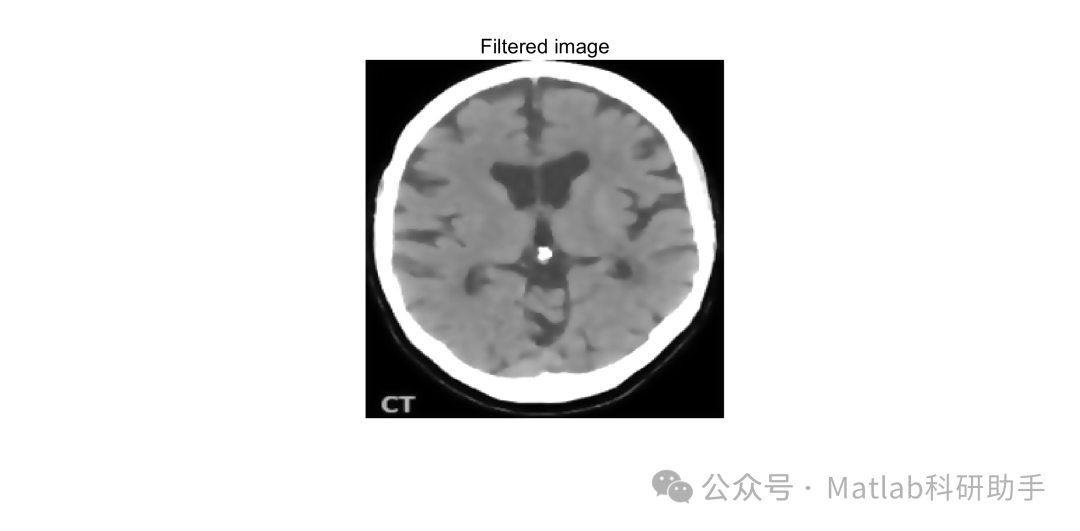

⛳️ 运行结果